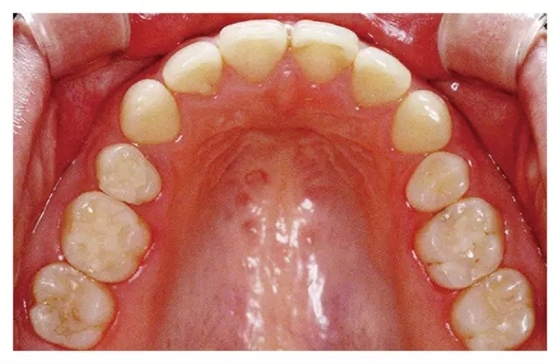

規(guī)格照片拍攝基準(zhǔn)

◇將大小調(diào)整至前牙到最后一顆臼齒均能看清

◇將牙齒正中部位放置于照片的中心位置

◇對(duì)焦在65·56牙齒附近。

◇調(diào)節(jié)反光鏡位置,使咬合面盡量能從正上方拍攝

◇對(duì)口腔進(jìn)行空氣干燥處理

① 使用咬合面專用鏡

② 在7·7牙的遠(yuǎn)心處插入反光鏡下端

① 選用比牙弓更大一些的咬合面專用鏡

② 反光鏡的下端放置在使得上頜最里面的臼齒后面還稍有空隙的位置

③ 在54·45牙齒附近放置兩個(gè)較小的開(kāi)口器